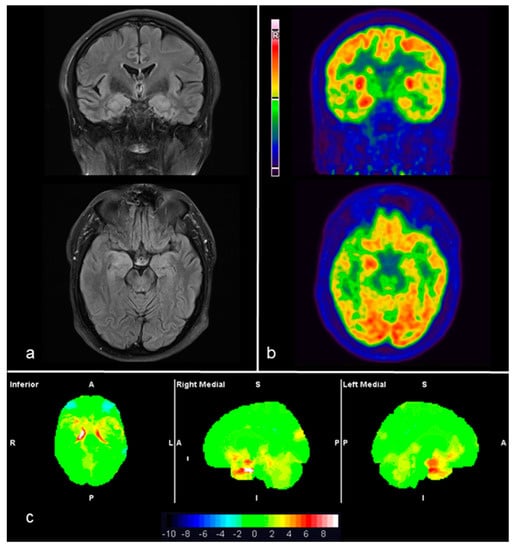

| 2 | LGI-1 | Frontal, Parietal, Temporal, Thalamus, Occipital. | L&R BC | Orbitofrontal, L Temporal | L&R BG, Cerebellar vermis; L&R MTL | Similar locations and R Parietal | Similar locations but more extended | L&R Lateral Frontal, L Temporal, L&R Parietal, R PC | L&R BG, Cerebellar vermis, L&R MTL | L&R Lateral Frontal, lateral Temporal, Parietal, PC | L&R BG, Cerebellar vermis, L&R MTL |